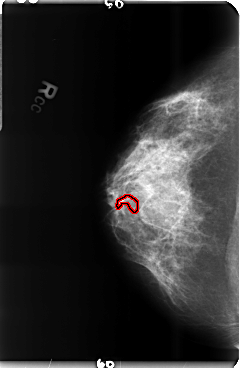

B_3517_1.RIGHT_CC

FILE: B_3517_1.RIGHT_CC.OVERLAY

TOTAL_ABNORMALITIES 1

ABNORMALITY 1

LESION_TYPE CALCIFICATION TYPE PLEOMORPHIC DISTRIBUTION LINEAR

ASSESSMENT 5

SUBTLETY 3

PATHOLOGY MALIGNANT

TOTAL_OUTLINES 2

BOUNDARY